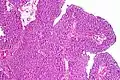

Histopathology of transitional carcinoma of the urinary bladder. Transurethral biopsy. Hematoxylin and eosin stain.

Transitional refers to the histological subtype of the cancerous cells as seen under a microscope.